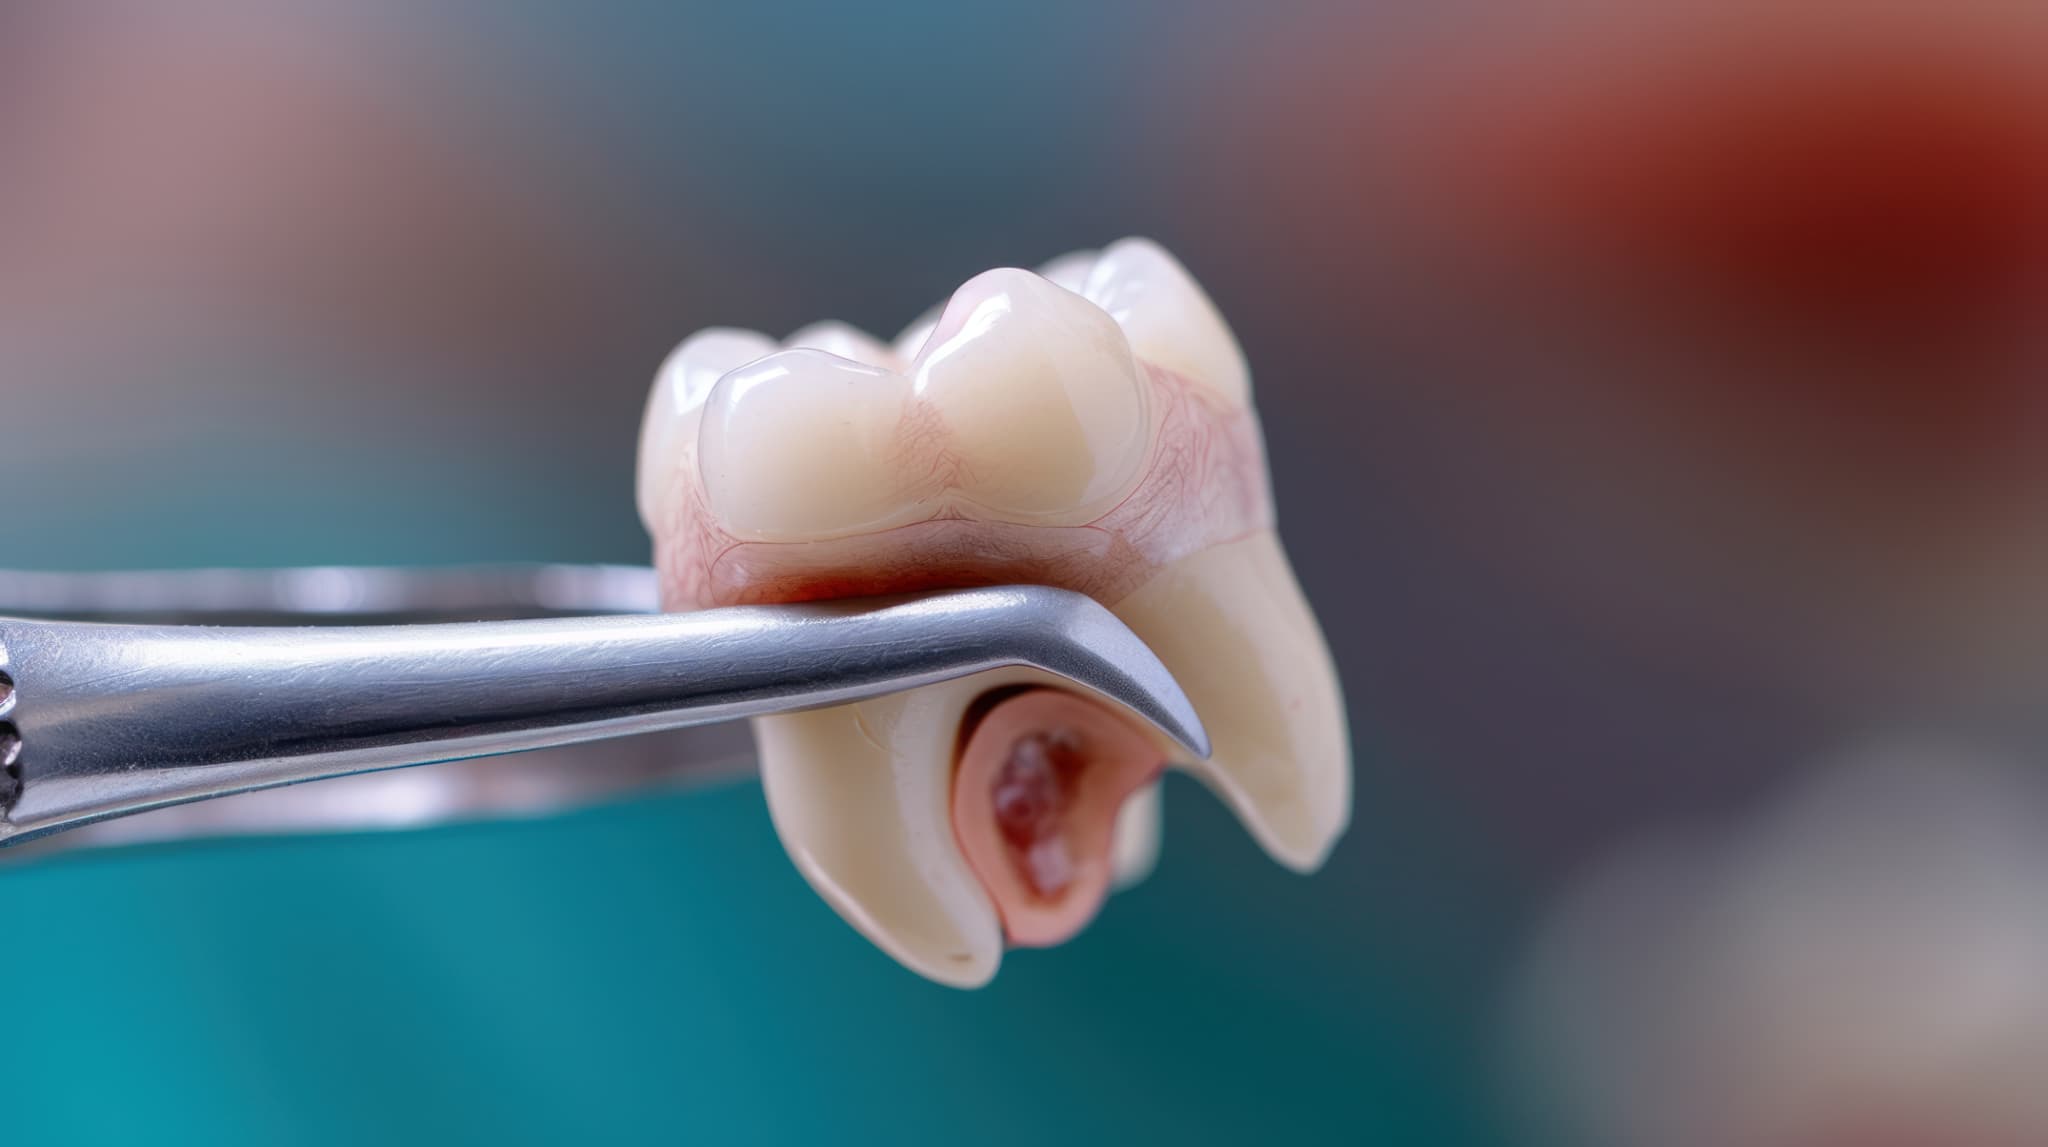

歯の分割・摘出

親知らずが斜めに生えていると、そのままでは取り出せないため、歯を分割してから取り除くことが一般的です。歯を数ミリ程度の厚さに分割しながら、少しずつ取り出していきます。